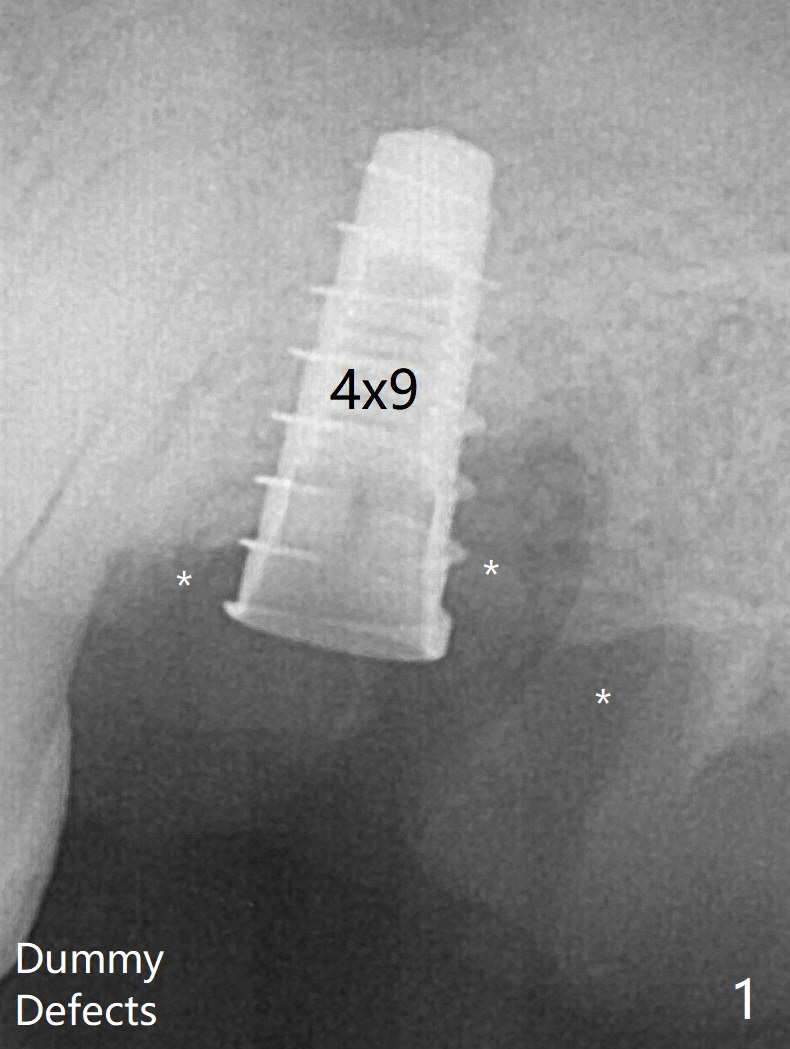

The 3 remaining sockets (Fig.1 *) around the final implant are filled with sticky bone (Fig.2 *).  The sockets are non-existing 1 year 7 months and 8 months postop (Fig.6,7 (BW)).